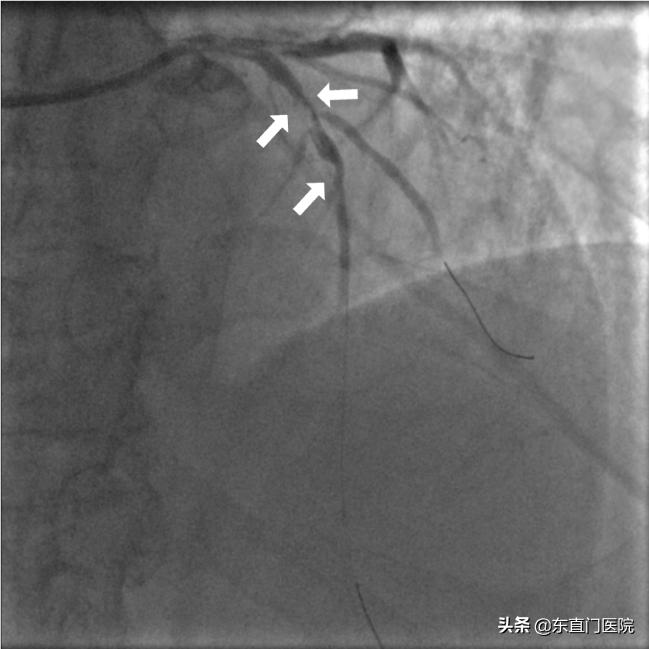

在IABP及血管活*药性**物(多巴胺、去甲肾上腺素等)的支持下,我科介入医生紧急进行冠脉造影,发现前降支(LAD)开口以远完全闭塞,未见供应LAD侧支循环。时间就是生命、时间就是心肌,我科介入医生迅速进行介入抢救,指引导管到位、导丝置入、血栓抽吸、球囊扩张开通血管一气呵成,从进入急诊室至球囊扩张的时间(Door to Balloon,D to B)为42分钟,从进入导管室至开通血管时间为17分钟。最终通过前降支直接PCI手术成功开通罪犯血管。期间险象频发,室性再灌注心律失常、血压测不出、无复流接踵而至,而其中无复流的发生是最灾难性的并发症,因为远端心肌并未得到血流灌注,梗死仍在继续!

术前冠脉造影:前降支从开口近段以远完全闭塞,仅残端(白色箭头)显影 |

PTCA后:闭塞段开通,见多发血栓影(白色箭头)伴重度狭窄 |